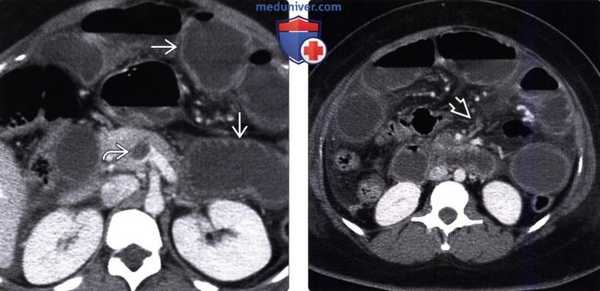

(Слева) На корональном изображении при КТ с контрастом у молодой женщины определяется окклюзия левой общей подвздошной артерии с коллатеральными сосудами, впадающими в левую бедренную артерию. Просвет верхней брыжеечной артерии также полностью перекрыт, сформированы коллатерали с расширенной нижней брыжеечной артерией.

(Справа) На сагиттальном изображении (КТ с контрастом) у этой же пациентки выявляется выраженное сужение начальных отделов чревного ствола, а также чередование участков стеноза и аневризматического расширения печеночной артерии. Эти изменения являются вторичными в результате артериита Такаясу. (Слева) На представленном объемном изображении сосудов в корональной плоскости выявлено диффузное неравномерное сужение в виде «нитки бус» печеночной артерии и ее ветвей. Эти изменения обусловлены артериитом Такаясу, при котором намного чаще поражается дуга аорты.

(Справа) При аксиальной КТ с контрастным усилением выявлены большие аневризмы внутрипеченочой ветви печеночной артерии и смещенной в сторону левой печеночной артерии в ее начальных отделах у пациента с узелковым полиартериитом. (Слева) При аксиальной нативной КТ у пациента с внезапно возникшими болями в боку с обеих сторон обнаружено двухстороннее кровоизлияние в паренхиму почек и в околопочечную клетчатку (скопление жидкости высокой плотности).

(Справа) При катетерной ангиографии у этого же пациента определяются множественные мелкие аневризмы ветвей почечной артерии, которые и стали причиной кровотечения. В последствии был подтвержден диагноз гранулематоза Вегенера. Кровоизлияние в паренхиму почек и в околопочечную клетчатку — типичные проявления васкулита при этом заболевании.